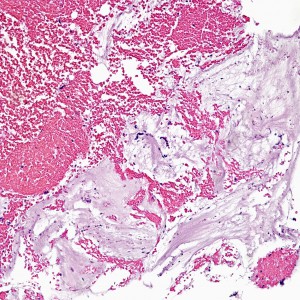

The biopsy contains rare areas like this with scan strips of surface tubal and lower uterine segment epithelium, but without any real appreciable glandular tissue.